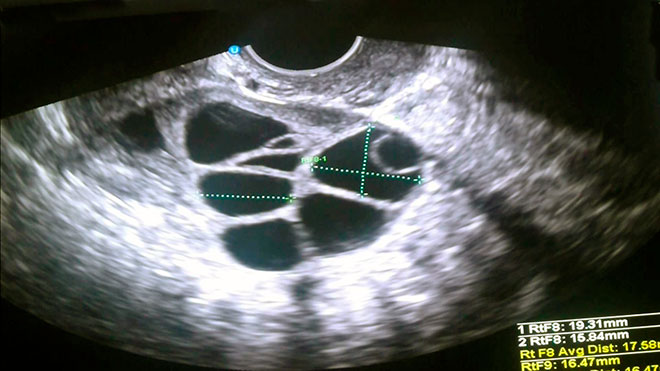

Режим инъекций гормонов называют протоколом или схемой стимуляции, и для каждой пациентки он подбирается индивидуально. При помощи УЗИ отслеживают рост фолликулов яичников, и когда они достигают определенного размера, яйцеклетки извлекают, аспирируя содержимое фолликулов.